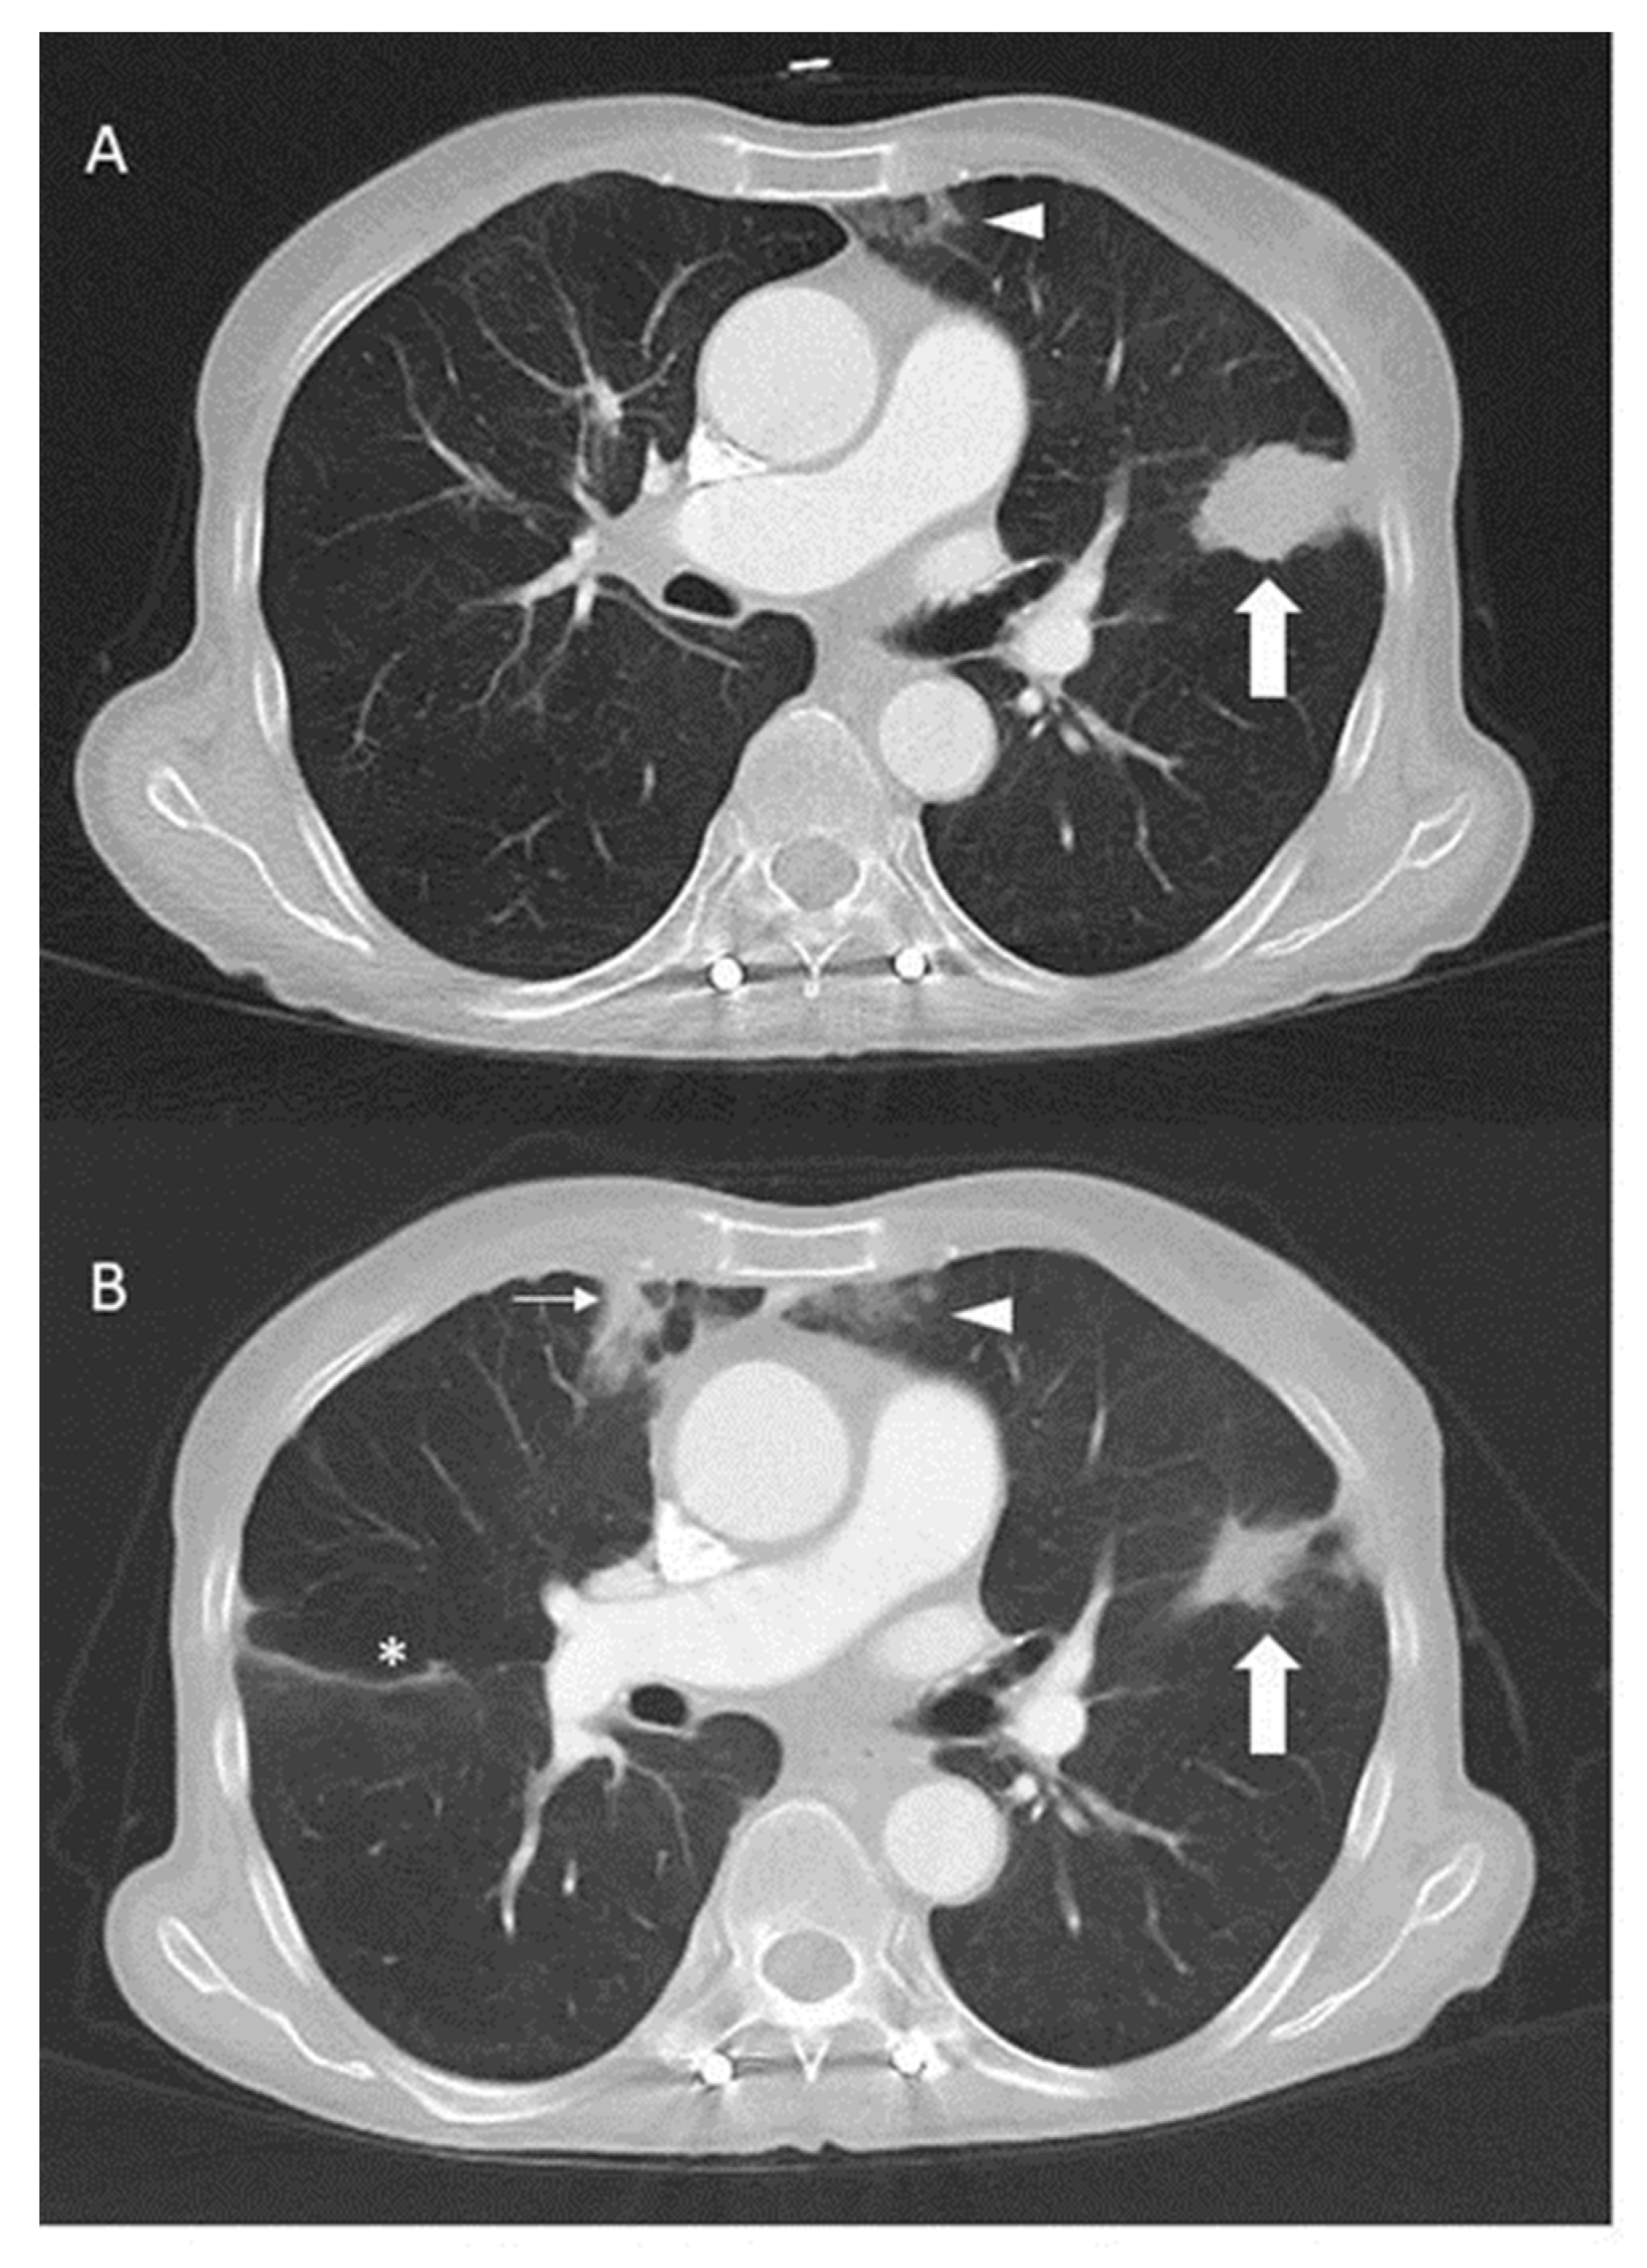

Third-line crizotinib monotherapy (250 mg twice per day) was started in February 2019, resulting in a partial remission lasting 17 months until July 2020, when the disease again progressed in the lungs and pleura. The molecular testing (Oncomine Focus Assay) of the tumour cells from the pleural effusion showed persistent EGFR p.L858R and HER2 p.S310F mutations, but no ROS1 fusion transcripts. In addition, the ROS1 FISH test was also negative. Due to the stable lesions interpreted as a response to the treatment outside of the thorax, crizotinib was continued and the pan-HER-inhibitor afatinib 30 mg daily was added to target EGFR and HER2 in October 2020. Crizotinib subsequently had to be reduced to 200 mg every other day due to oedema and afatinib to 20 mg at 2 out of 3 days due to skin toxicity. This time, a partial response with a clinical benefit could be observed for two years (Figure 2).

Figure 2.

Computed tomography of the thorax with contrast before (A) and three months after the addition (B) of crizotinib to afatinib in October 2020. The mass (thick arrow) in the lingula responded to therapy. Incidental findings include subpleural consolidations (thin arrow) and dystelectasis (arrowheads) and slight interlobar effusion (*) on the right side.